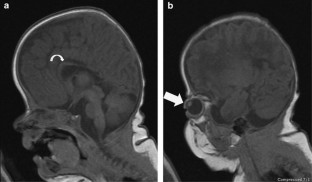

Herman, T., Siegel, M. Apert syndrome with omphalocele. J Perinatol 30, 695–697 (2010). https://doi.org/10.1038/jp.2010.72